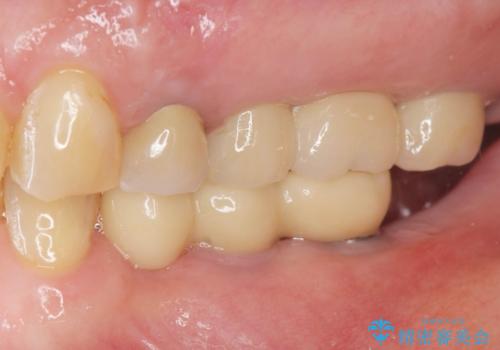

- 奥歯を虫歯で失ってしまい、しっかりと噛めるようになりたい、と希望され来院されました。

3本の歯(クラウン)を2本のインプラントで支えるインプラントブリッジによる咬合機能の回復を計画します。

治療後、しっかりと咬合機能が回復され見た目の自然さにも満足いただくことができました。